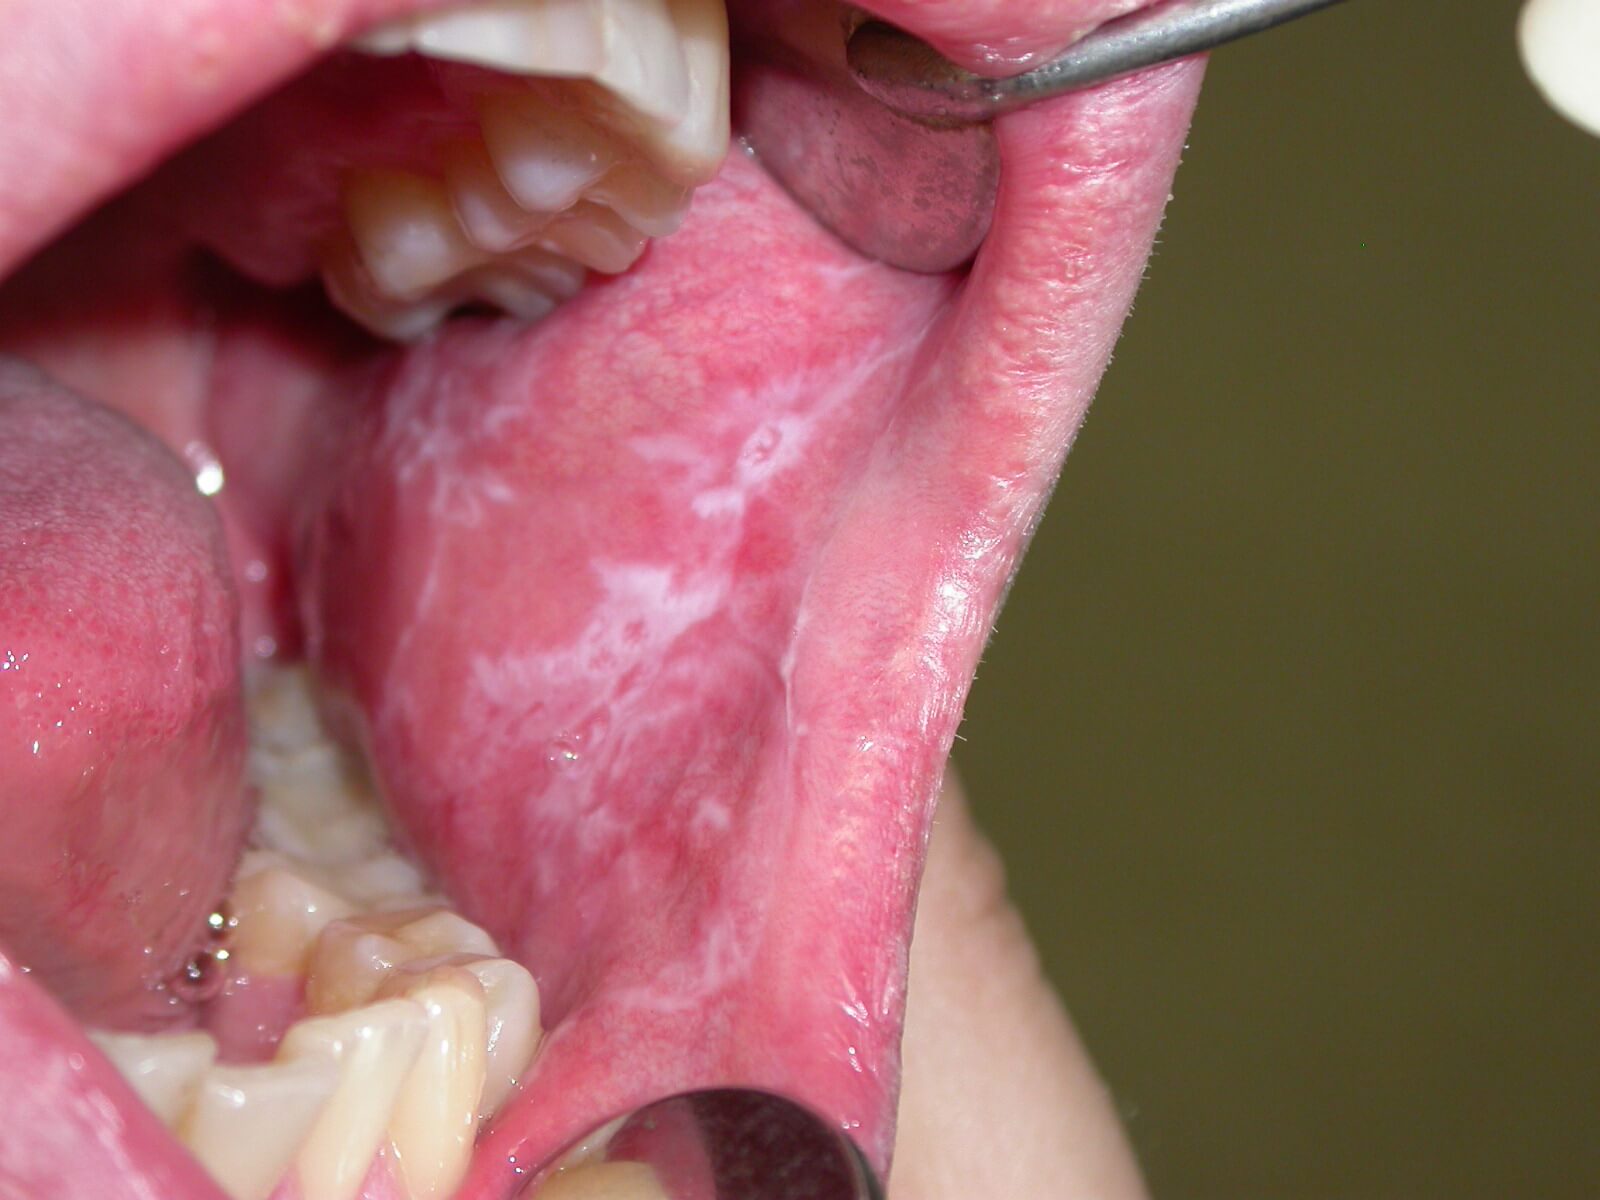

Если говорить о показаниях к применению препарата, то они представлены незначительными инфекциями ротовой полости.

В частности, речь идёт о кандидозе, боли в горле, гингивите, афтозных язвах, неприятном запахе изо рта.